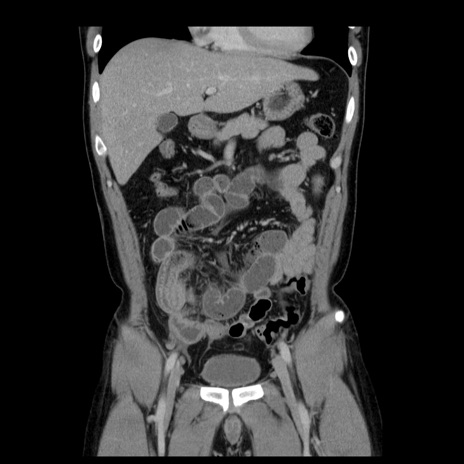

横断像

【症例】30歳代男性

【主訴】腹痛、嘔吐

【現病歴】昨晩から突然の腹痛あり、その後嘔吐、軟便も出現。腹痛が改善しないため救急搬送となる。2日前にしめ鯖の食事歴あり。

【身体所見】意識清明、苦悶様、BP 135/90mmHg、BT 35.7℃、腹部:平坦、やや硬、心窩部〜臍部に自発痛、圧痛あり、筋性防御+、反跳痛-

【データ】WBC 8100、CRP 0.57